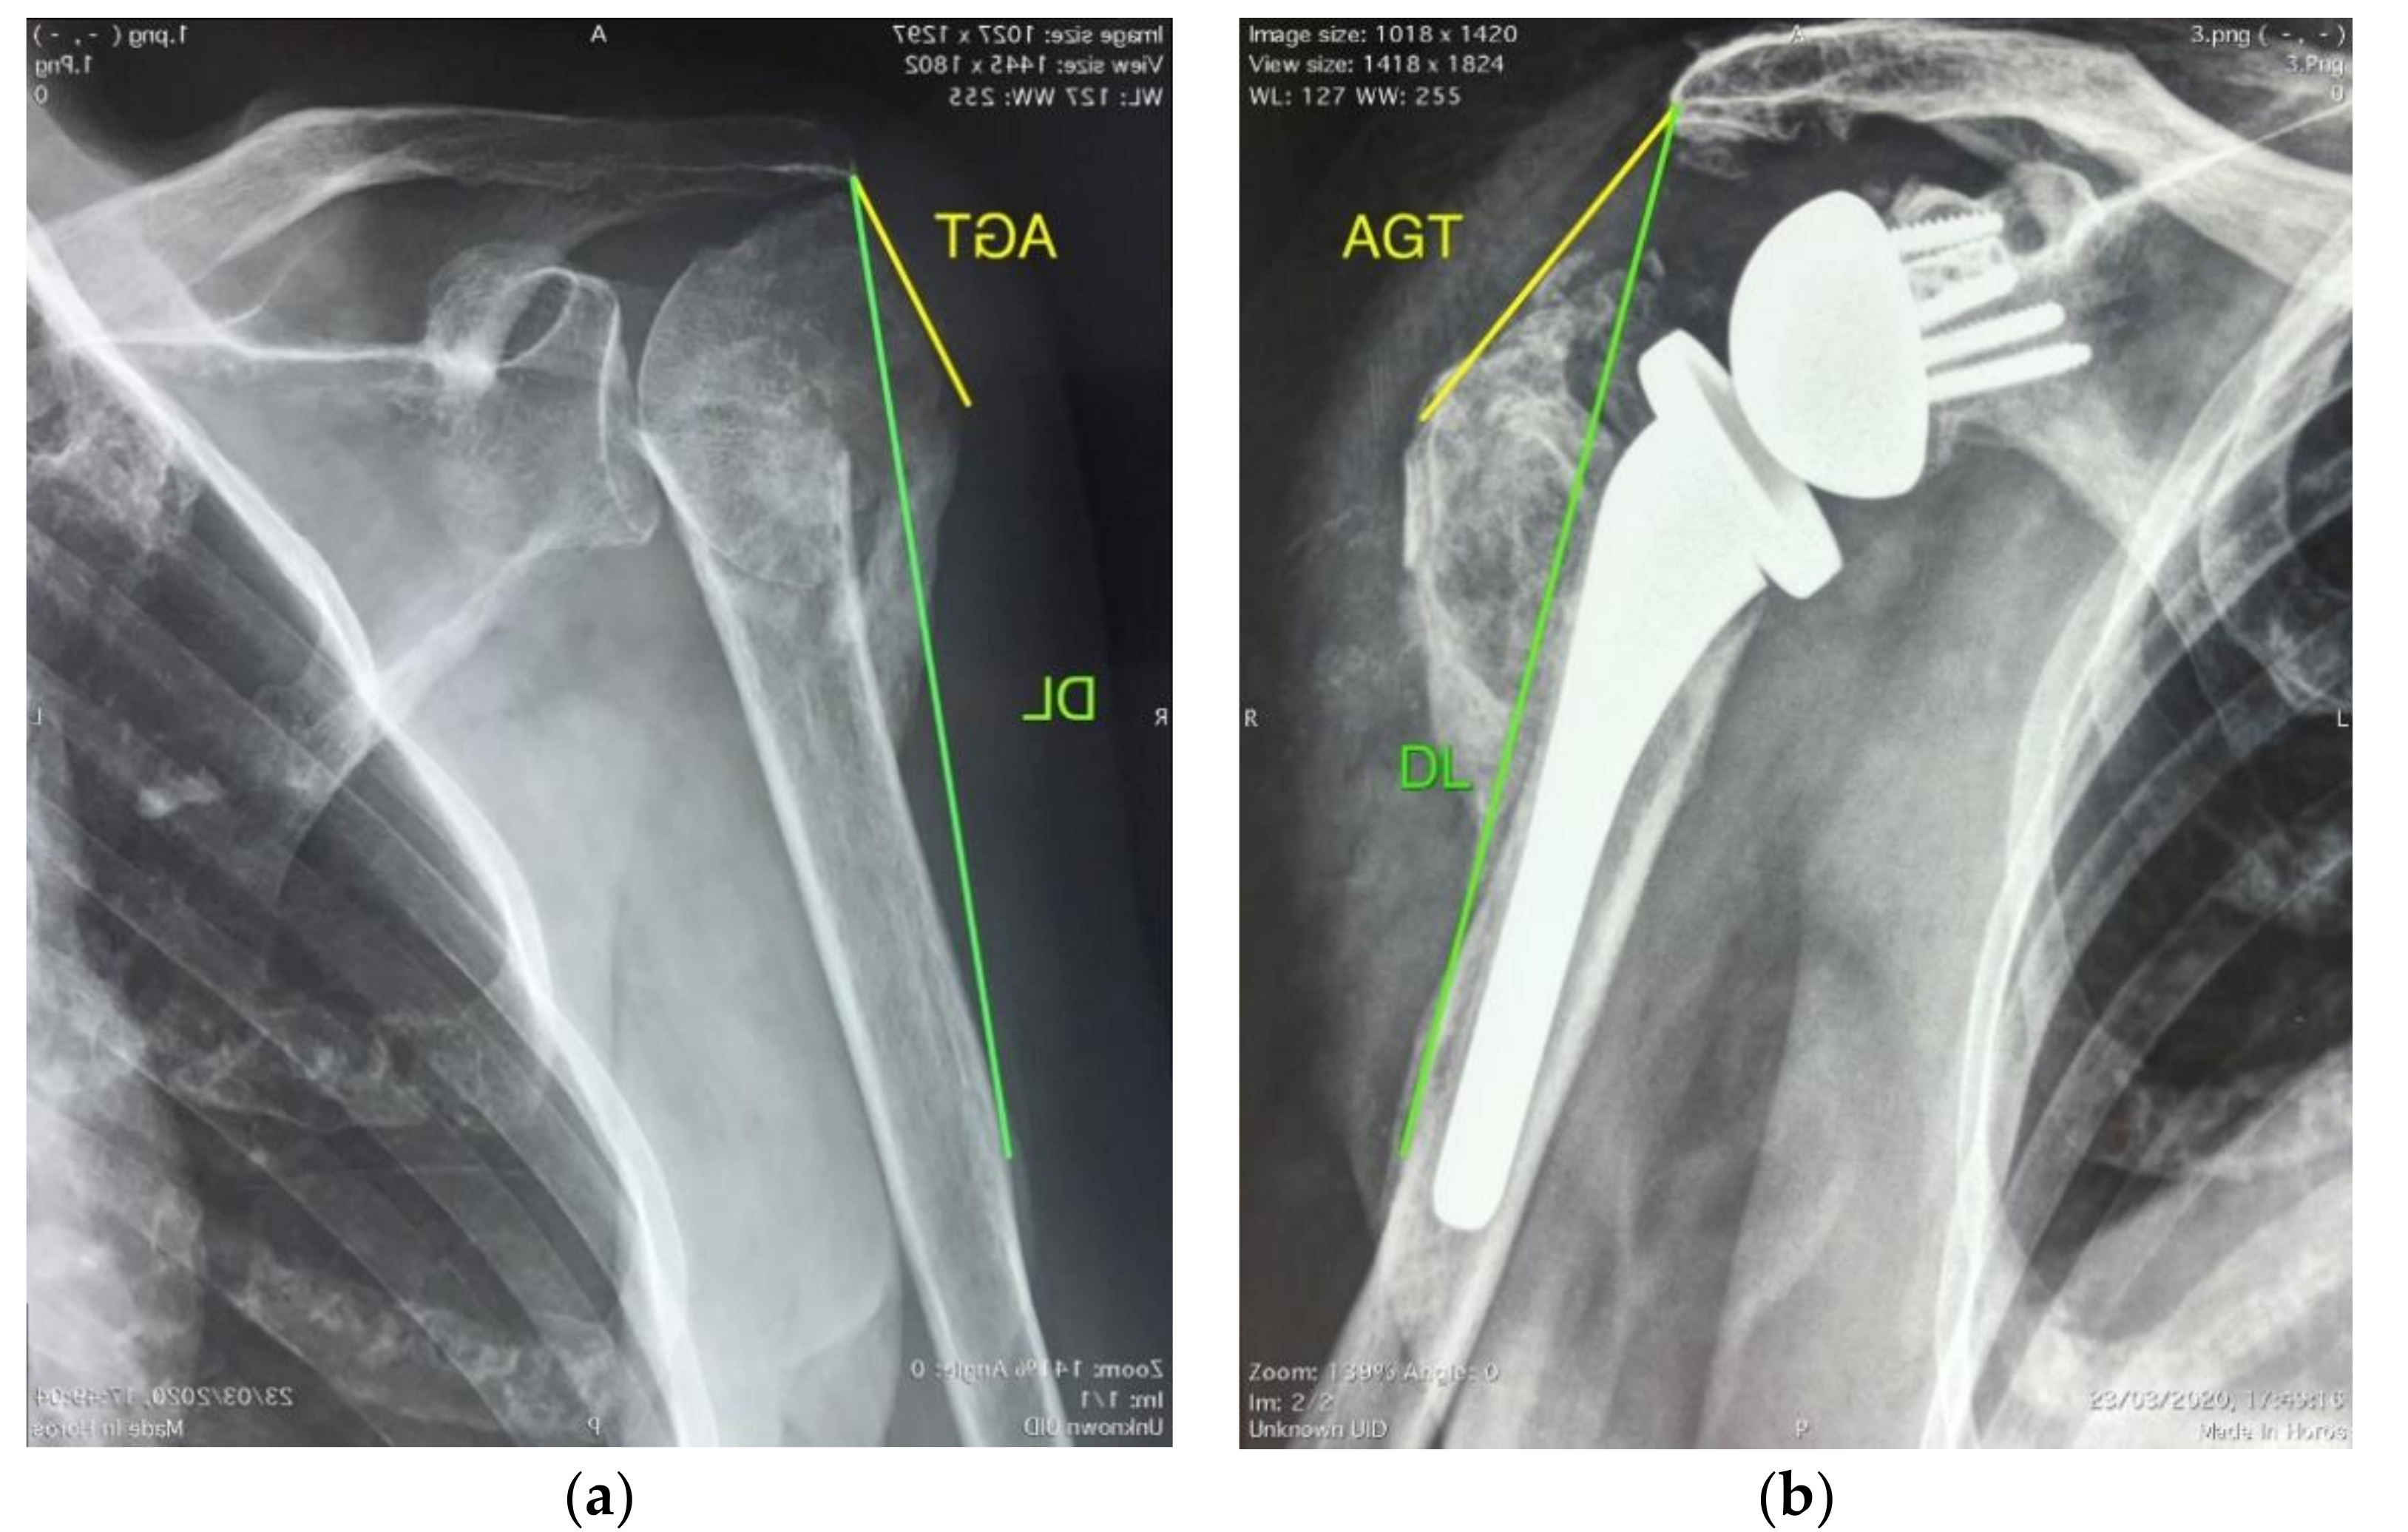

2.3. Radiographic Evaluation

3.2. Radiographic